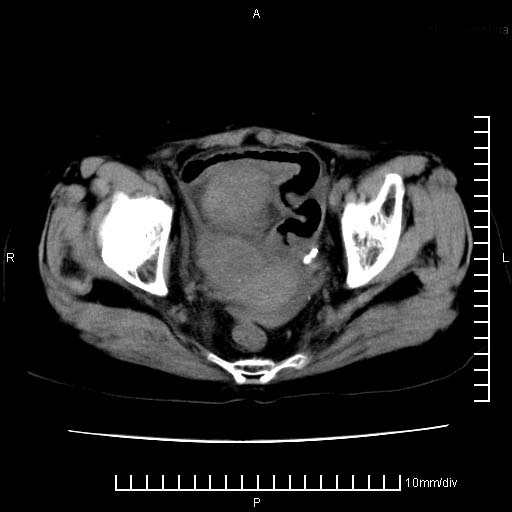

下腹疼痛2月,加重并呕吐2天,下腹压痛,反跳痛。白细胞1万2.

下腹至盆腔较大包块,与邻近肠管关系密切,下腹疼痛2月,加重并呕吐2天,下腹压痛,反跳痛。白细胞1万2.

由于没有做肠道准备很难分清是哪根肠管,但看位置考虑为升结肠回盲部的问题,我首先考虑化脓性阑尾炎,不除外结肠癌合并感染化脓。建议做增强进一步明确。

补充:道格拉斯腔内有积液,且密度较高,显然提示有感染。

考虑右侧卵巢囊肿伴感染可能性大。

附件实性肿块有坏死 考虑卵巢癌

来源于附件占位—多考虑:卵巢癌!